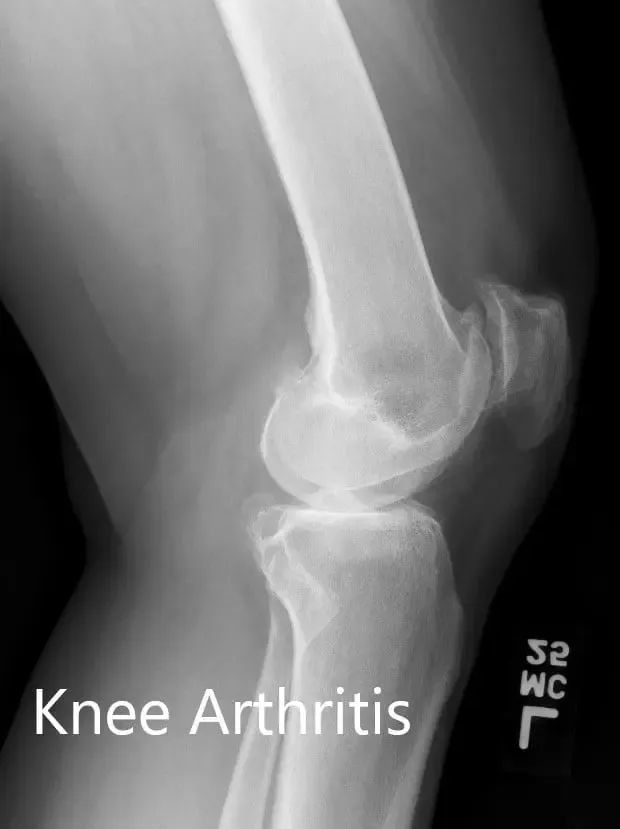

The images studies revealed tricompartmental osteoarthritis of the left knee. Considering lifestyle limiting knee pain, the patient was advised to undergo customized left knee replacement. Risks, benefits, and alternatives were discussed with the patient and her family. They all agreed to go ahead with the surgery.

Preoperative X-ray of the left knee showing AP and lateral views